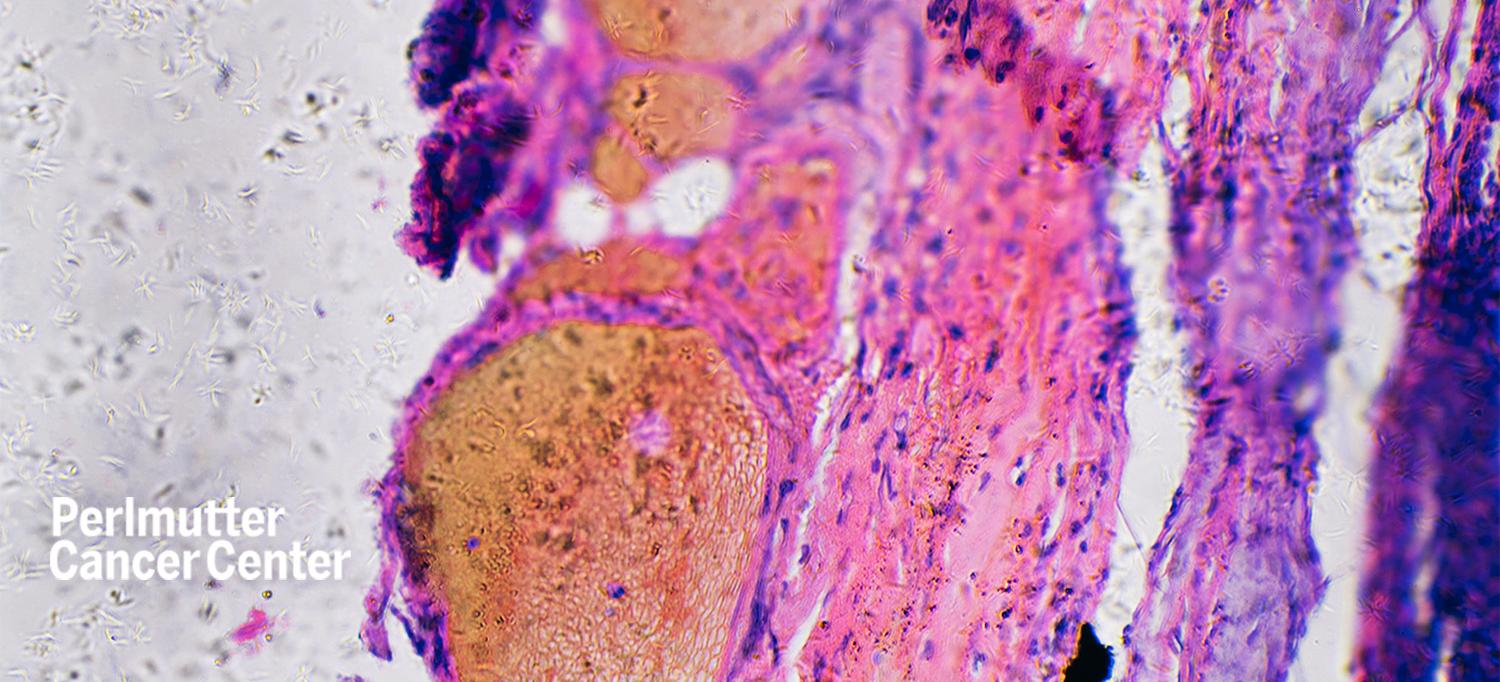

A phase 3 clinical trial testing a type of individualized cell therapy that uses tumor-infiltrating lymphocytes (TILs)—surgically obtained white blood cells that have infiltrated a person’s tumor—significantly improved progression-free survival when compared with standard immunotherapy with ipilimumab in people with unresectable stage 3C-4 melanoma. The study results were presented at the 2022 European Society for Medical Oncology Congress.

“The results of this trial may fuel further research of TIL in other cancer types, potentially demonstrating benefit in many other solid tumors and expanding available treatments for patients,” Maya Dimitrova, MD, clinical assistant professor in the Department of Medicine at NYU Grossman School of Medicine and a medical oncologist at NYU Langone Health’s Perlmutter Cancer Center, tells Medscape.